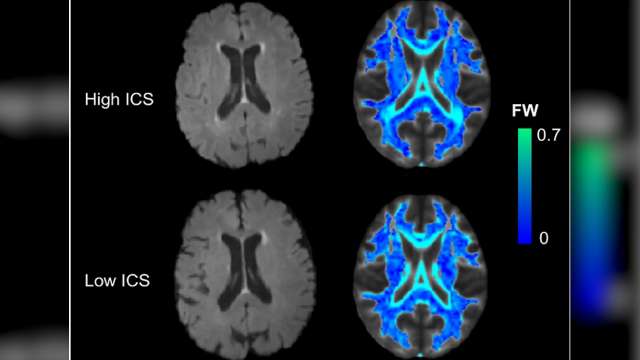

Stroke and Dementia Research

Dr. Jason Hinman's lab is focused on identifying the molecular pathways that interface the two most common neurologic disorders: stroke and dementia. The goal is to develop new diagnostic tools to better recognize patients who are at risk for post-stroke cognitive impairment and dementia, and develop treatments based on discoveries they've made in the lab.